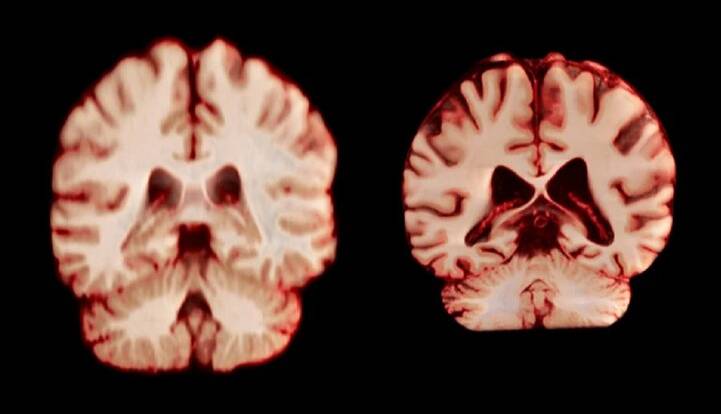

سیاست و بازاریابی - ایسنا / مغز زنان کُندتر پیر می‌شود، اما به نظر نمی‌رسد که این موضوع آنها را از ابتلا به نوع شایع زوال عقل محافظت کند.

بر اساس یک مطالعه طولی که امروز در مجموعه مقالات آکادمی ملی علوم منتشر شد، در طول پیری، مردان در مقایسه با زنان، کاهش حجم بیشتری را در مناطق بیشتری از مغز تجربه می‌کنند. نویسندگان معتقدند این بدان معناست که تغییرات مغزی مرتبط با سن توضیح نمی‌دهد که چرا زنان بیشتر از مردان به بیماری آلزایمر مبتلا می‌شوند.

زنان تقریبا دو برابر مردان به بیماری آلزایمر مبتلا می‌شوند و پیری بزرگترین عامل خطر برای این بیماری است. این موضوع باعث شده است که تحقیقاتی در مورد تفاوت‌های جنسیتی مرتبط با سن در مغز انجام شود. آن راوندال، دانشجوی دکترا در دانشگاه اسلو و یکی از نویسندگان این مقاله، می‌گوید: اگر مغز زنان بیشتر تحلیل رفته باشد، این می‌تواند به توضیح شیوع بالاتر آلزایمر در آنها کمک کند.

راوندال اضافه می‌کند که تحقیقات قبلی که تفاوت‌های جنسیتی در پیری مغز را بررسی می‌کردند، نتایج متفاوتی را نشان داده‌اند. چندین مطالعه نشان داده‌اند که مردان در مقایسه با زنان، کاهش بیشتری در کل ماده خاکستری و اندازه هیپوکامپ را تجربه می‌کنند، در حالی که سایر تحقیقات، کاهش شدیدتر ماده خاکستری در زنان را گزارش کرده‌اند.

جدیدترین مطالعه شامل بیش از 12 هزار و 500 اسکن مغزی تصویربرداری تشدید مغناطیسی (MRI) از 4726 نفر بود که حداقل دو اسکن برای هر نفر، با فاصله متوسط ‌سه سال انجام شده بود که به بیماری آلزایمر یا هرگونه اختلال شناختی مبتلا نبودند و به عنوان شرکت‌کننده کنترل در 14 مجموعه داده بزرگتر قرار داشتند. محققان با بررسی عواملی از جمله ضخامت ماده خاکستری و اندازه نواحی مرتبط با بیماری آلزایمر، مانند هیپوکامپ که برای حافظه ضروری است، نحوه تغییر ساختار مغز افراد را در طول زمان مقایسه کردند.

به طور کلی، مردان در مقایسه با زنان، کاهش حجم بیشتری را در مناطق بیشتری از مغز تجربه کردند. به عنوان مثال، قشر پس مرکزی که مسئول پردازش احساسات لامسه، درد و دما و همچنین موقعیت و حرکات بدن است، در مردان سالانه 2.0 درصد و در زنان سالانه 1.2 درصد کاهش یافت.

کامفور می‌گوید نتایج نشان می‌دهد که مردان سریع‌تر از زنان پیر می‌شوند. همچنین امید به زندگی در مردان کمتر است.